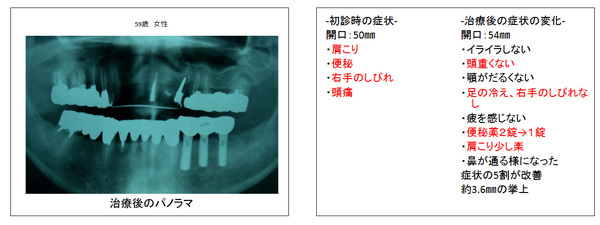

インプラント治療後の噛み合わせ治療の症例

他院でインプラント治療後に再度噛み合わせ治療をした3症例

インプラントの埋入は、大きく分けて、部分的に失った場所に少数のインプラントを埋入することで他の歯を削らなくて歯が固定されるケースと多数のインプラントを埋入することで義歯から解放され、固定ブリッジになるケースが考えられます。

すなわち、噛み合わせが低くなることで、噛み合わせのバランスが崩れ全身的に見て顔貌、姿勢は歪み、自律神経は乱れ、免疫力、ホルモン力も低下を来しその結果、健康をも害しているのです。

インプラントの固定する数ヶ月の間の仮歯を用いて、噛み合わせ治療を行い、高くなる事でいかに健康を取り戻すことが出来るかということを自分の身体で体感して、診断するのです。

そして、自分の健康に適する顎の位置でブリッジなり、義歯を作ることで審美的にも機能的にも満足され、なおかつ健康を取り戻すことが出来るのです。